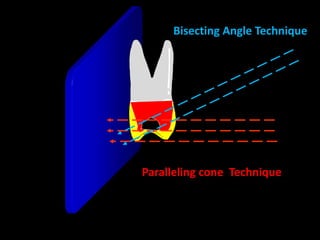

2. The paralleling cone technique provides accurate images with little magnification and no superimposition but is more difficult for patients. The bisecting angle technique is easier for patients but results in more image distortion.